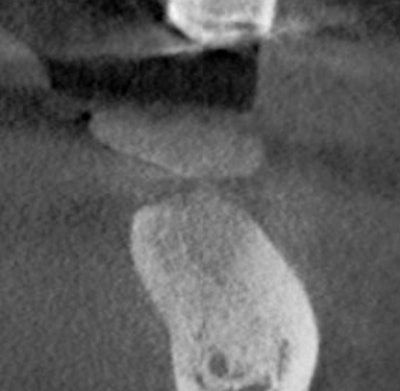

Oral exam revealed a lower left second molar tooth with class III mobility and severe occlusal wear. Periapical pathology was present because of a poorly treated root canal. A CBCT scan gave us a clear understanding that tooth #18 was hopeless and was literally floating in pathology.

Incidental findings were present: a mesiodens in the area of #9 with an associated asymptomatic periapical lesion.